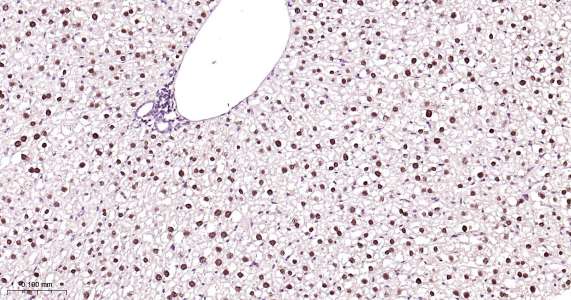

Immunohistochemical analysis of paraffin embedded mouse liver tissue slide using IHC0413M (Mouse HNF4A IHC Kit).